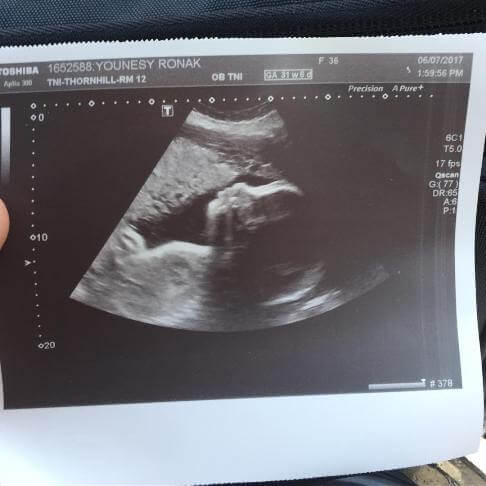

روناک یونسی بازیگر کشورمان این روزها دوران بارداری خود را سپری می کند. این بازیگر ۳۶ ساله و همسرش منتظر بدنیا آمدن فرزند دوم شان هستند.

محسن میری نوشت: آقای میری کوچک

سونوگرافی روناک یونسی